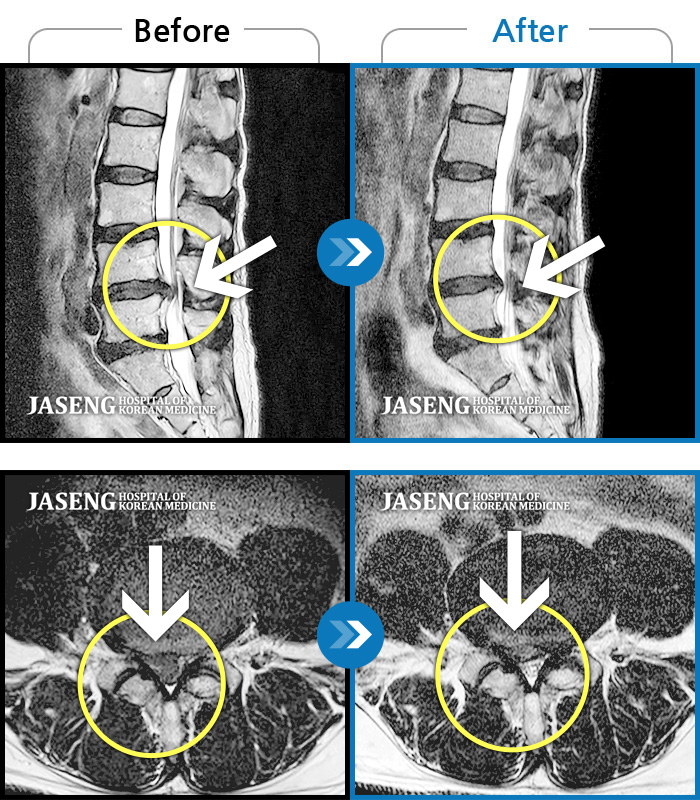

허리디스크

인천 · 조남훈 원장

허리가 너무 아프고 다리가 저려요.

촬영시기

2018.04.23 ~ 2025.12.05

2025.12.19